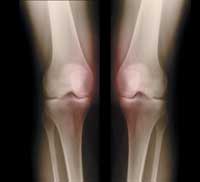

Медицинская справка: вторичный синовит